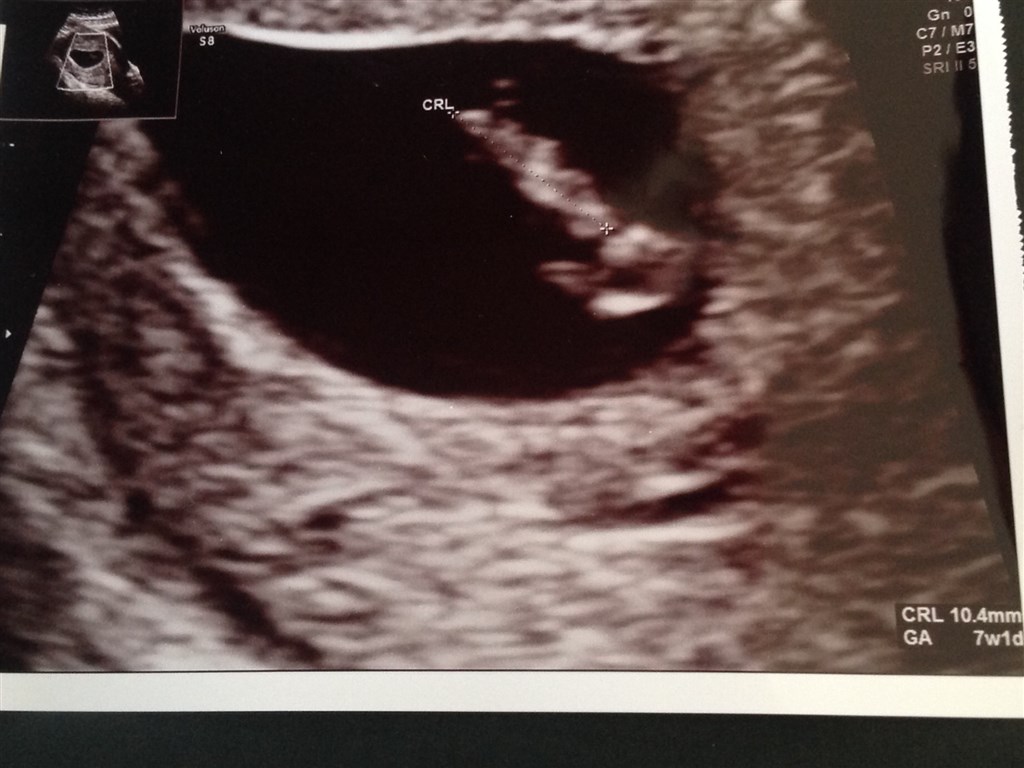

Jeg er ifølge min sidste menstruation 7+1 idag, og sørme om scannings sygeplejersken ikke målte baby til at være præcis 7+1 så det passer jo helt perfekt

Dens lille hjerte bankede derud af og den gav os oven i købet et bette spjæt med som vi tydeligt kunne se